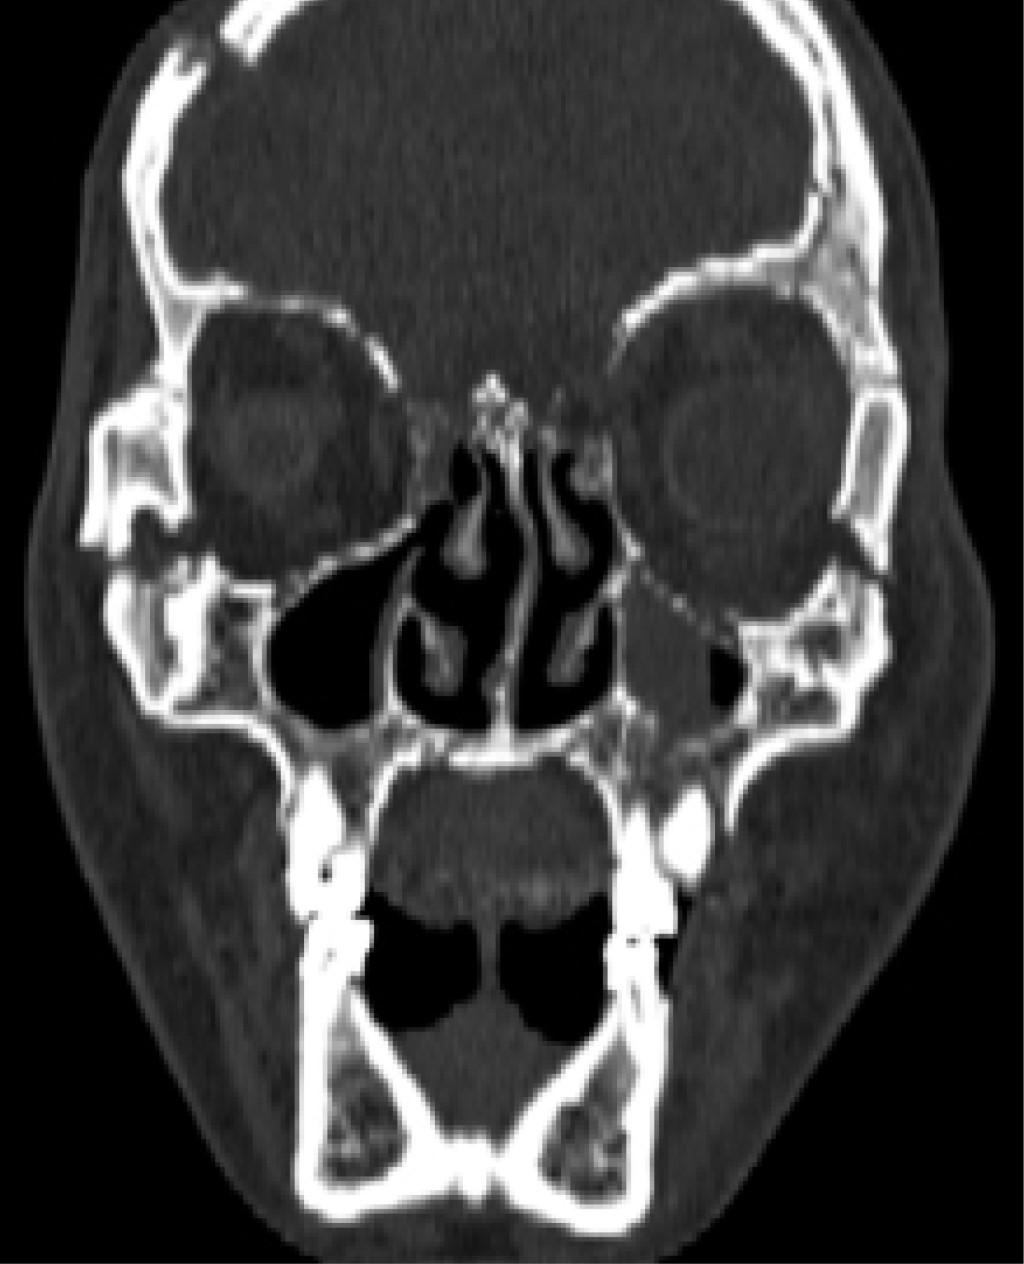

Se trata de paciente masculino de 37 años, sin antecedentes médicos conocidos, quien llega al Servicio de Emergencia del Hospital Universitario de Caracas posterior a sufrir politraumatismo por accidente en vehículo en movimiento tipo moto en calidad de piloto. Es evaluado por el Servicio de Emergencia para control de la vía aérea y columna cervical, respiración, circulación, valoración del estado neurológico y exposición y control ambiental (ABCDE), tomografía computarizada (Figuras 1 y 2) y posteriormente realizan síntesis de tejidos de heridas lacerantes en región facial. Es llevado a mesa operatoria para realizar traqueotomía, drenaje de hematoma epidural y colocación de ivy loops y posteriormente ingresado en la Unidad de Cuidados Intensivos para estabilización y control. Al examen maxilofacial presentó equimosis bipalpebral bilateral, puntos de sutura en región frontal bilateral que discurren a párpado superior izquierdo, puntos de sutura en región infraorbitaria izquierda, región nasogeniana izquierda, heridas dermoabrasivas en región frontal bilateral, dorso y punta de la nariz, región infraorbitaria izquierda, nasogeniana izquierda y región mentoniana; al examen intraoral apertura bucal limitada, edentulismo parcial bimaxilar, hematoma en fondo de vestíbulo superior izquierdo y mucosa yugal izquierda, puntos de sutura en fondo de vestíbulo izquierdo, fijación intermaxilar con ivy loops y movilidad de OD 1.2.

La tomografía computarizada (TC) con reconstrucción volumétrica 3D se ha vuelto el estándar de oro en examen imagenológico para pacientes con trauma en la región facial, ya que presenta información 1:1 del patrón de fractura.4

La tomografía computarizada (TC) con reconstrucción volumétrica 3D es el examen imagenológico de elección para evaluar el patrón de fractura en pacientes con trauma facial. Proporciona información detallada y precisa sobre las fracturas, lo que permite una mejor planificación quirúrgica. En este caso, se utilizó una TC postoperatoria para evaluar los resultados de la cirugía.9

Figura 2